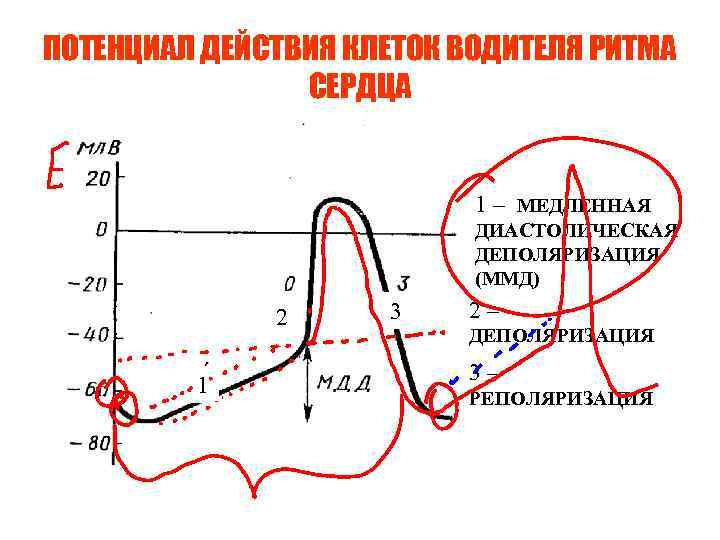

ПОТЕНЦИАЛ ДЕЙСТВИЯ КЛЕТОК ВОДИТЕЛЯ РИТМА СЕРДЦА 1 – МЕДЛЕННАЯ ДИАСТОЛИЧЕСКАЯ ДЕПОЛЯРИЗАЦИЯ (ММД) 2 1 3 2– ДЕПОЛЯРИЗАЦИЯ 3– РЕПОЛЯРИЗАЦИЯ

ПОТЕНЦИАЛ ДЕЙСТВИЯ КЛЕТОК ВОДИТЕЛЯ РИТМА СЕРДЦА 1 – МЕДЛЕННАЯ ДИАСТОЛИЧЕСКАЯ ДЕПОЛЯРИЗАЦИЯ (ММД) 2 1 3 2– ДЕПОЛЯРИЗАЦИЯ 3– РЕПОЛЯРИЗАЦИЯ